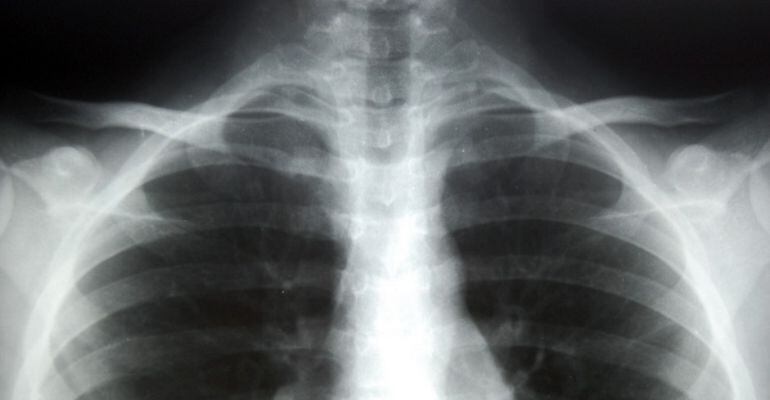

Imatge d'una radiografia d'uns pulmons / FLICKR